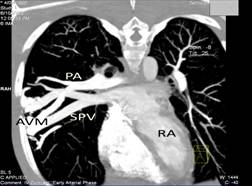

Complete blood count revealed polycythaemia (Hb of 210 g/L; HCT 0.64 L/L). Computed Tomography (CT) brain showed evidence of a right pontine infarct with no suggestion of cerebral arteriovenous malformation. Chest radiograph showed a faint right mid-zone opacity. Transthoracic echocardiography showed no evidence of septal wall defects or large vessel anomalies and no pulmonary hypertension. Plain CT of the chest suggested the presence of a PAVM (Figure 1). This was confirmed by CT pulmonary angiogram which revealed a solitary PAVM with two feeder vessels in the lower lobe of the right lung (Figure 2 and 3).

Figure 1: CT scan of the chest suggested the presence of right PAVM.